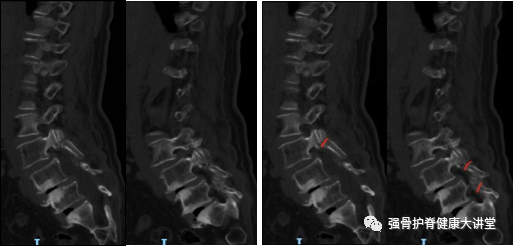

图1

图1、2 为63岁女性,诊断为腰椎峡部裂滑脱(L3-L5),红色线为CT矢状位右侧峡部裂位置,黄色线为CT矢状位左侧峡部裂位置。